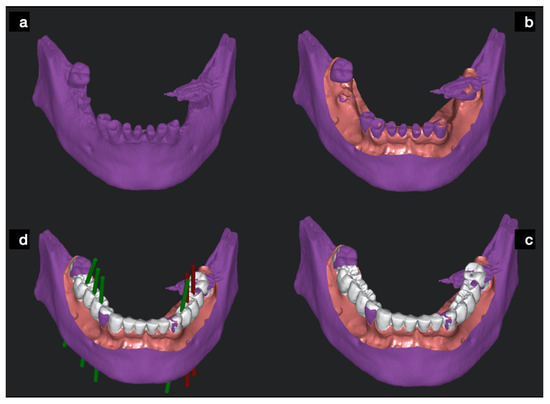

2.2. Dynamic Computer Aided Implantology Workflow (ND)

2.2.1. Plan

2.2.2. Trace

2.2.3. Place